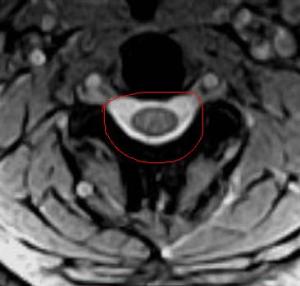

Praticamente questo meccanismo provoca una compressione sul midollo senza che si sia un’ernia discale a spingere! La compressione non è su una radice, ma sul midollo stesso.